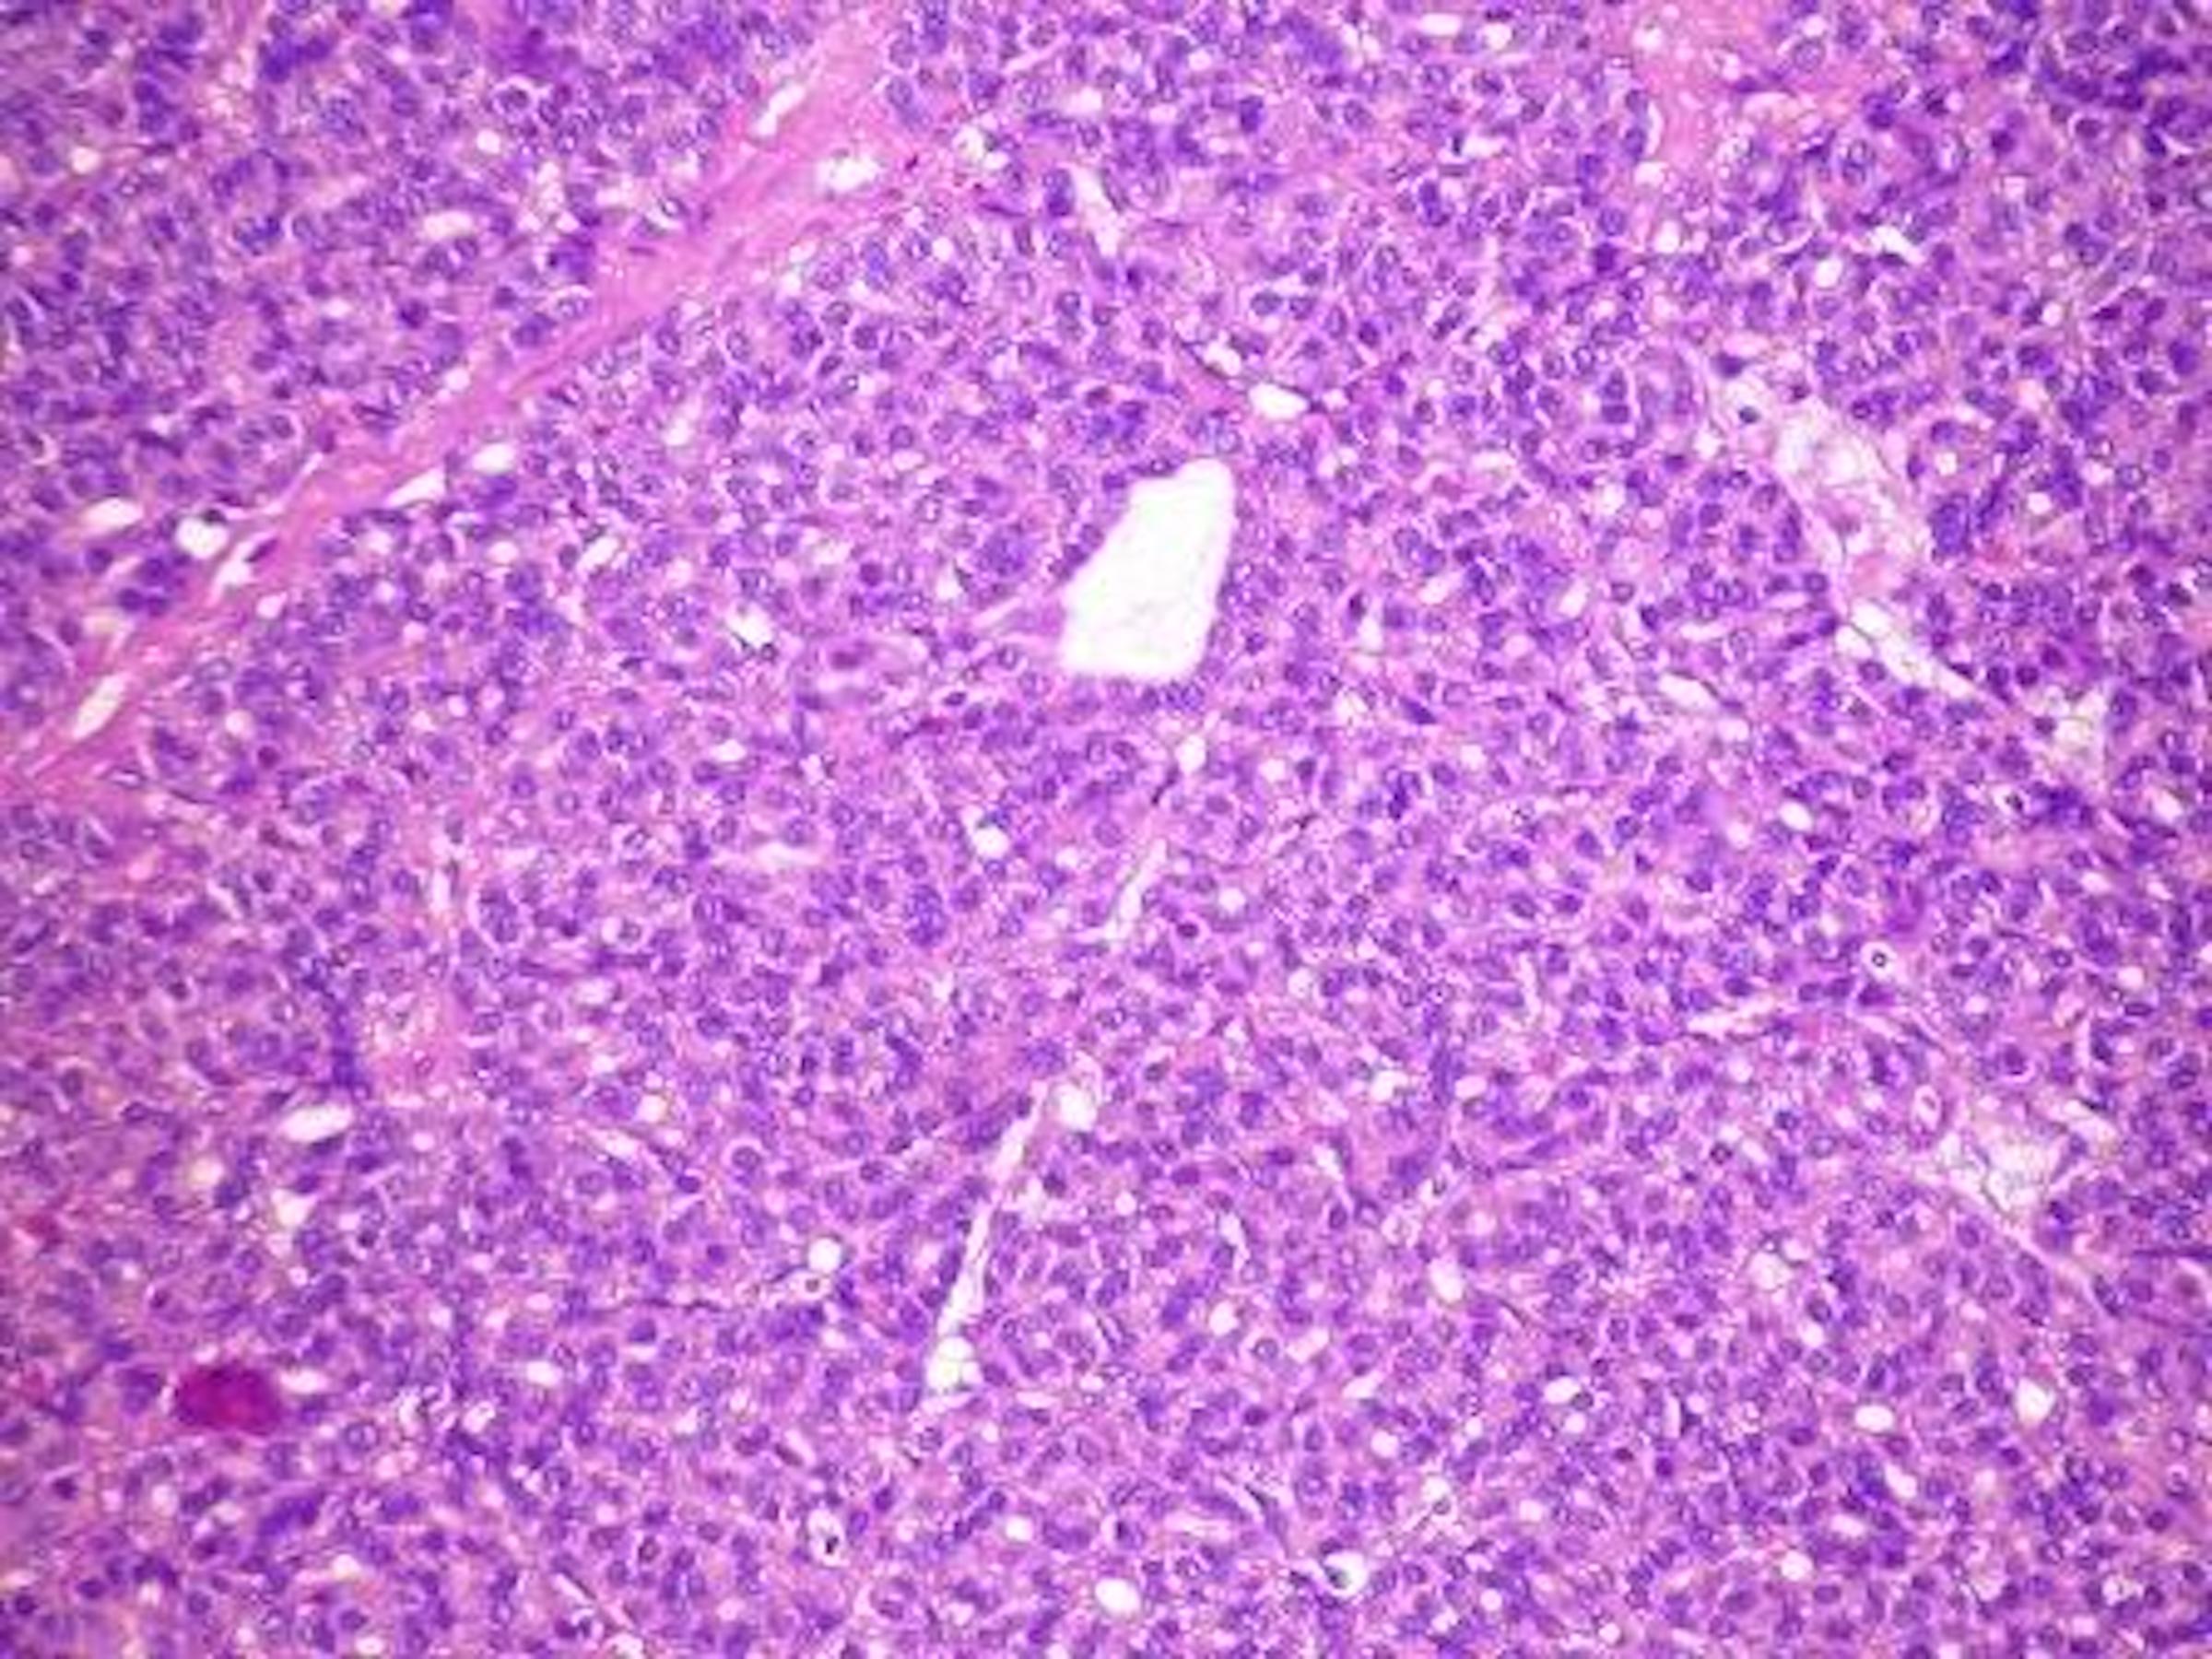

Microscopic (histologic) description

- Architectural patterns (can be seen in any combination)

- Microfollicular (fetal): smaller follicles, small amount of intraluminal colloid

- Solid / trabecular (embryonal): minimal or no colloid

- Cuboidal to low columnar cells

- Small round nuclei, smooth nuclear boundary, uniformly hyperchromatic or euchromatic, dense chromatin, absent nuclear features of papillary thyroid carcinoma, nuclear score 0 or 1 (JAMA Oncol 2016;2:1023)

- Inconspicuous nucleoli

- Mitoses are uncommon

- Scant stroma

- Variants

- Follicular adenoma with bizarre nuclei: may be seen after radiation exposure and in hyperfunctioning adenoma

Microscopic (histologic) images

Contributed by Shipra Agarwal, M.D., Andrey Bychkov, M.D., Ph.D., Mark R. Wick, M.D., Asmaa Gaber Abdou, M.D. and AFIP

Atypical adenomas: